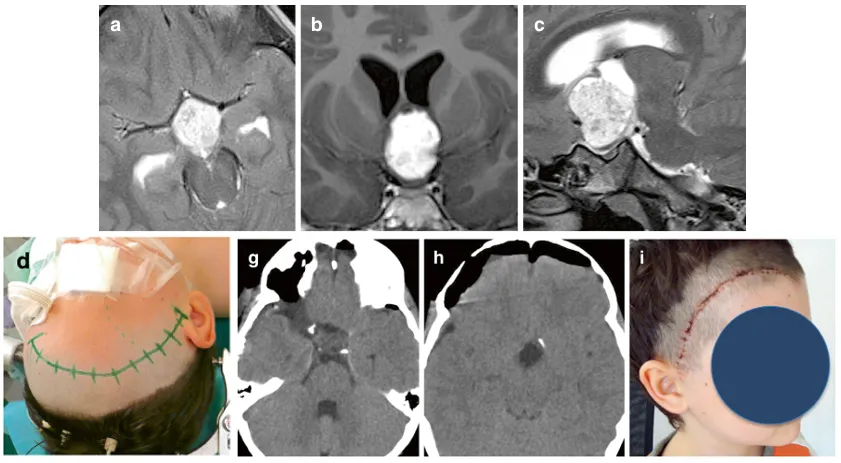

图:一名2岁男性患儿鞍上一囊实性、显著强化的占位性病变延伸至左侧颞叶,经左翼点开颅入路行肿瘤全切除术。术后MRI证实肿瘤全切,患儿状况良好。

图:一名8岁男性患儿因视路-下丘脑胶质瘤累及第三脑室出现视力受损,采用右侧眶颧开颅入路经终板入路成功实现肿瘤全切。术后早期CT证实全切,美容效果满意。